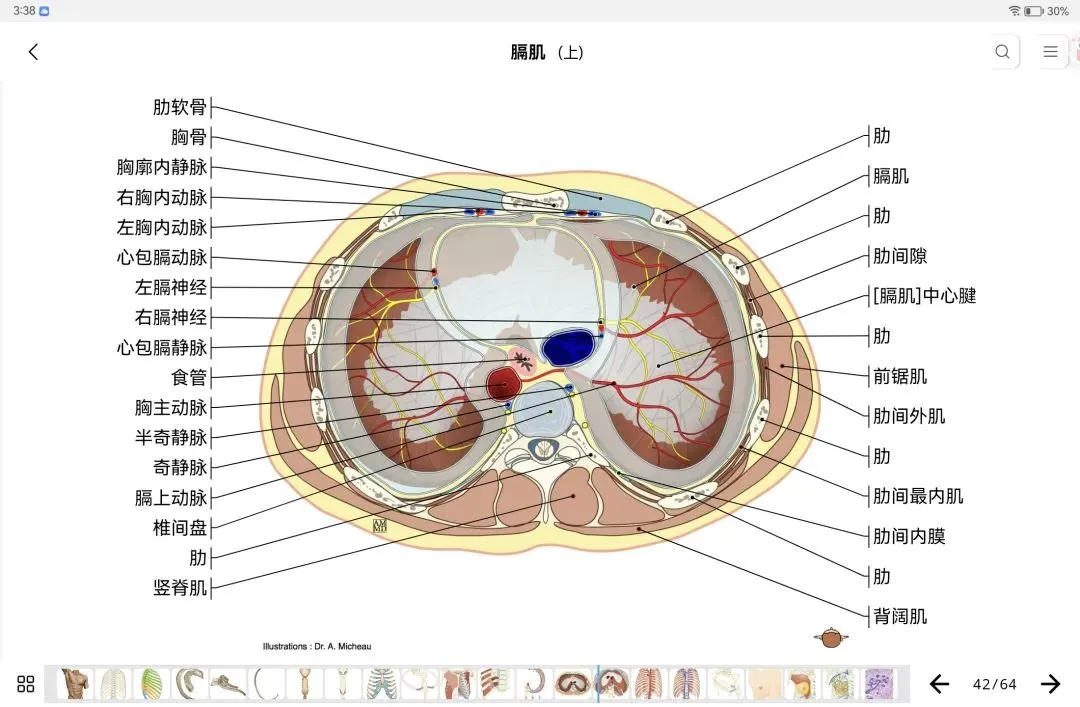

覆盖了X光、CT、MRI、断层大体解剖、核医学、介入造影、医学插图等多个模块,覆盖全身各个系统的影像解剖(正常解剖结构,无病例),其中的解剖结构高达87万个,结构标注超精细,超高清图像,历时两年研发设计完成✅。